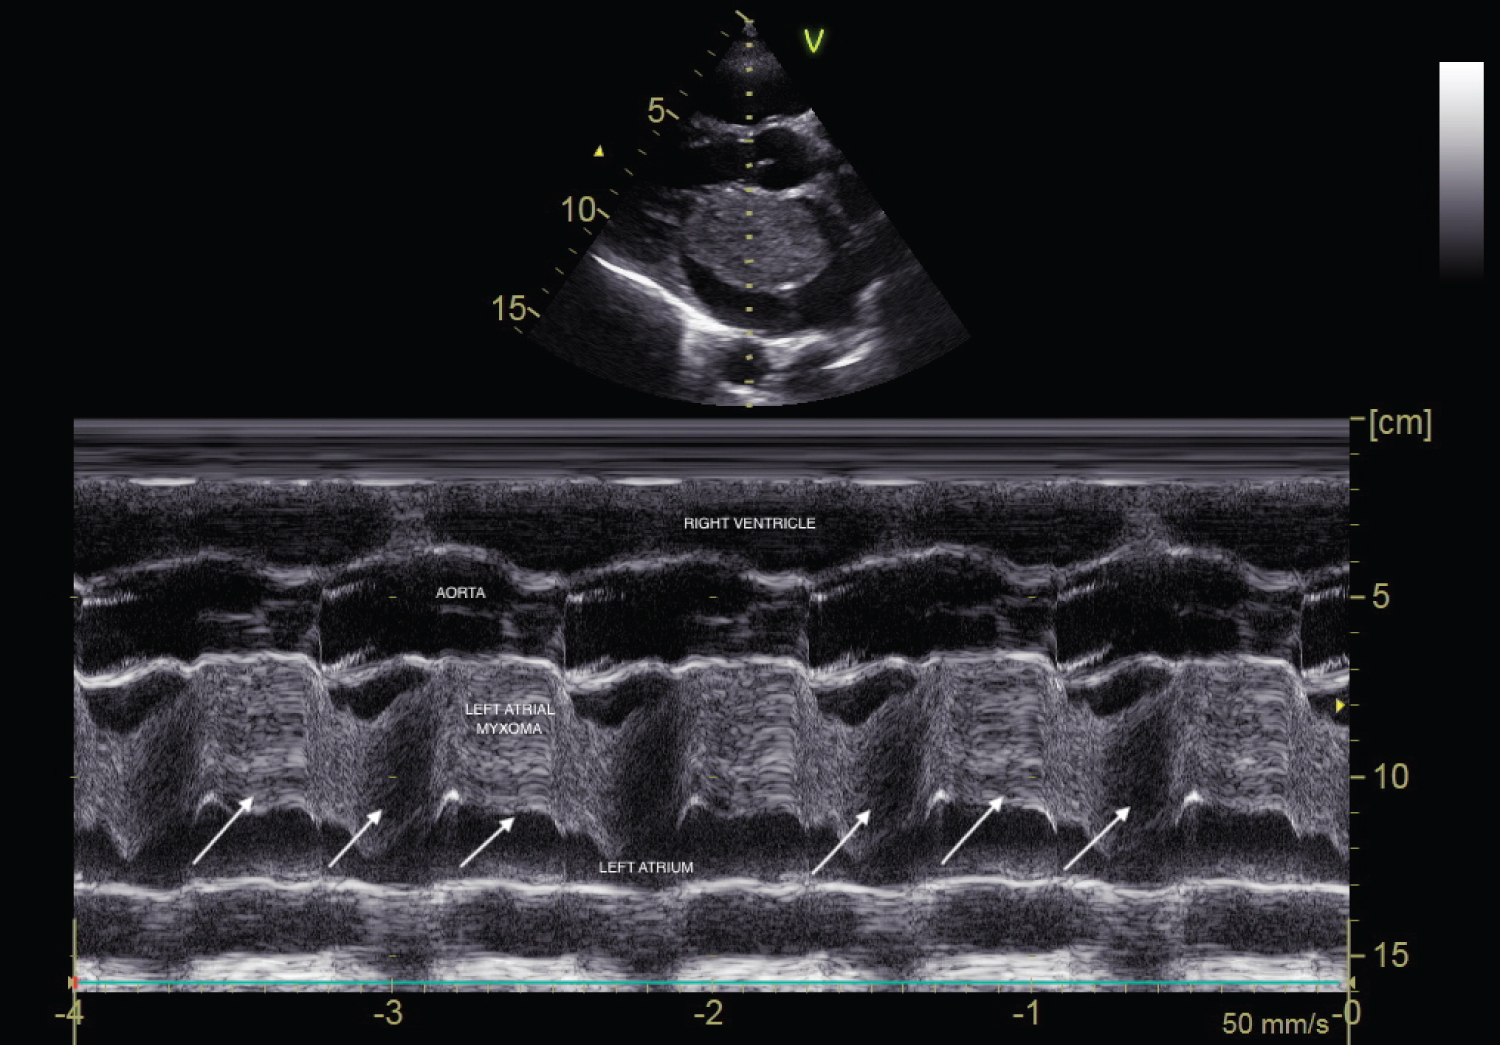

A 45-year-old male was referred to the out-patient clinic of Cardiology department with complaints of recurrent lightheadedness and dizziness on standing and changing postures in bed for past 3 months. He was normotensive, and non-diabetic person with no history of chest pain, dyspnea, palpitations, TIA or stroke. His ECG was unremarkable. CVS examination revealed a low pitch, early diastolic sound along with a soft systolic murmur at the apex. 2D-Echocardiographic study revealed a large, pedunculated mass in the left atrium with stalk attached to fossa ovalis region (Figure 1, Figure 3, Video 1 and Video 2). M-mode echocardiography showed a mass 'plopping' out through LA producing a characteristic multiple diastolic echoes within the mitral orifice as well as systolic echoes within the left atrium (Figure 2). Patient underwent emergency operation for resection of LA mass (Figure 4). Histopathological findings were consistent with myxoma. There was no recurrence of myxoma 6 months post-excision.

Figure 2: M-mode echocardiography in parasternal long axis view showing systolic and diastolic echoes produced in left atrium as a result of plopping of tumour across mitral orifice.